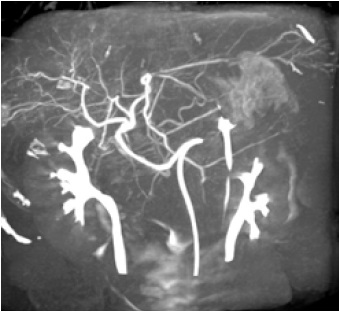

Режим Dynamic trace

Dynamic trace – режим дослідження кінцівок, передбачає рух деки столу за напрямком поширення контрастної речовини по периферичних судинах в режимі рентгенографії.

Програмне забезпечення Parametric Imaging

Використовується для візуальної оцінки і аналізу функціональності кровообігу. Параметричне зображення показує всю послідовність зображень у вигляді одного складеного зображення, яке характеризує динаміку контрастної речовини та полегшує візуальну оцінку. Крива залежності інтенсивності від часу аналізується для кожного окремого пікселя.

Для покращення розуміння кровотоку в судинах можливим є створення відео за рахунок пересування по кольоровій шкалі (Color Coded Circulation (CCC).